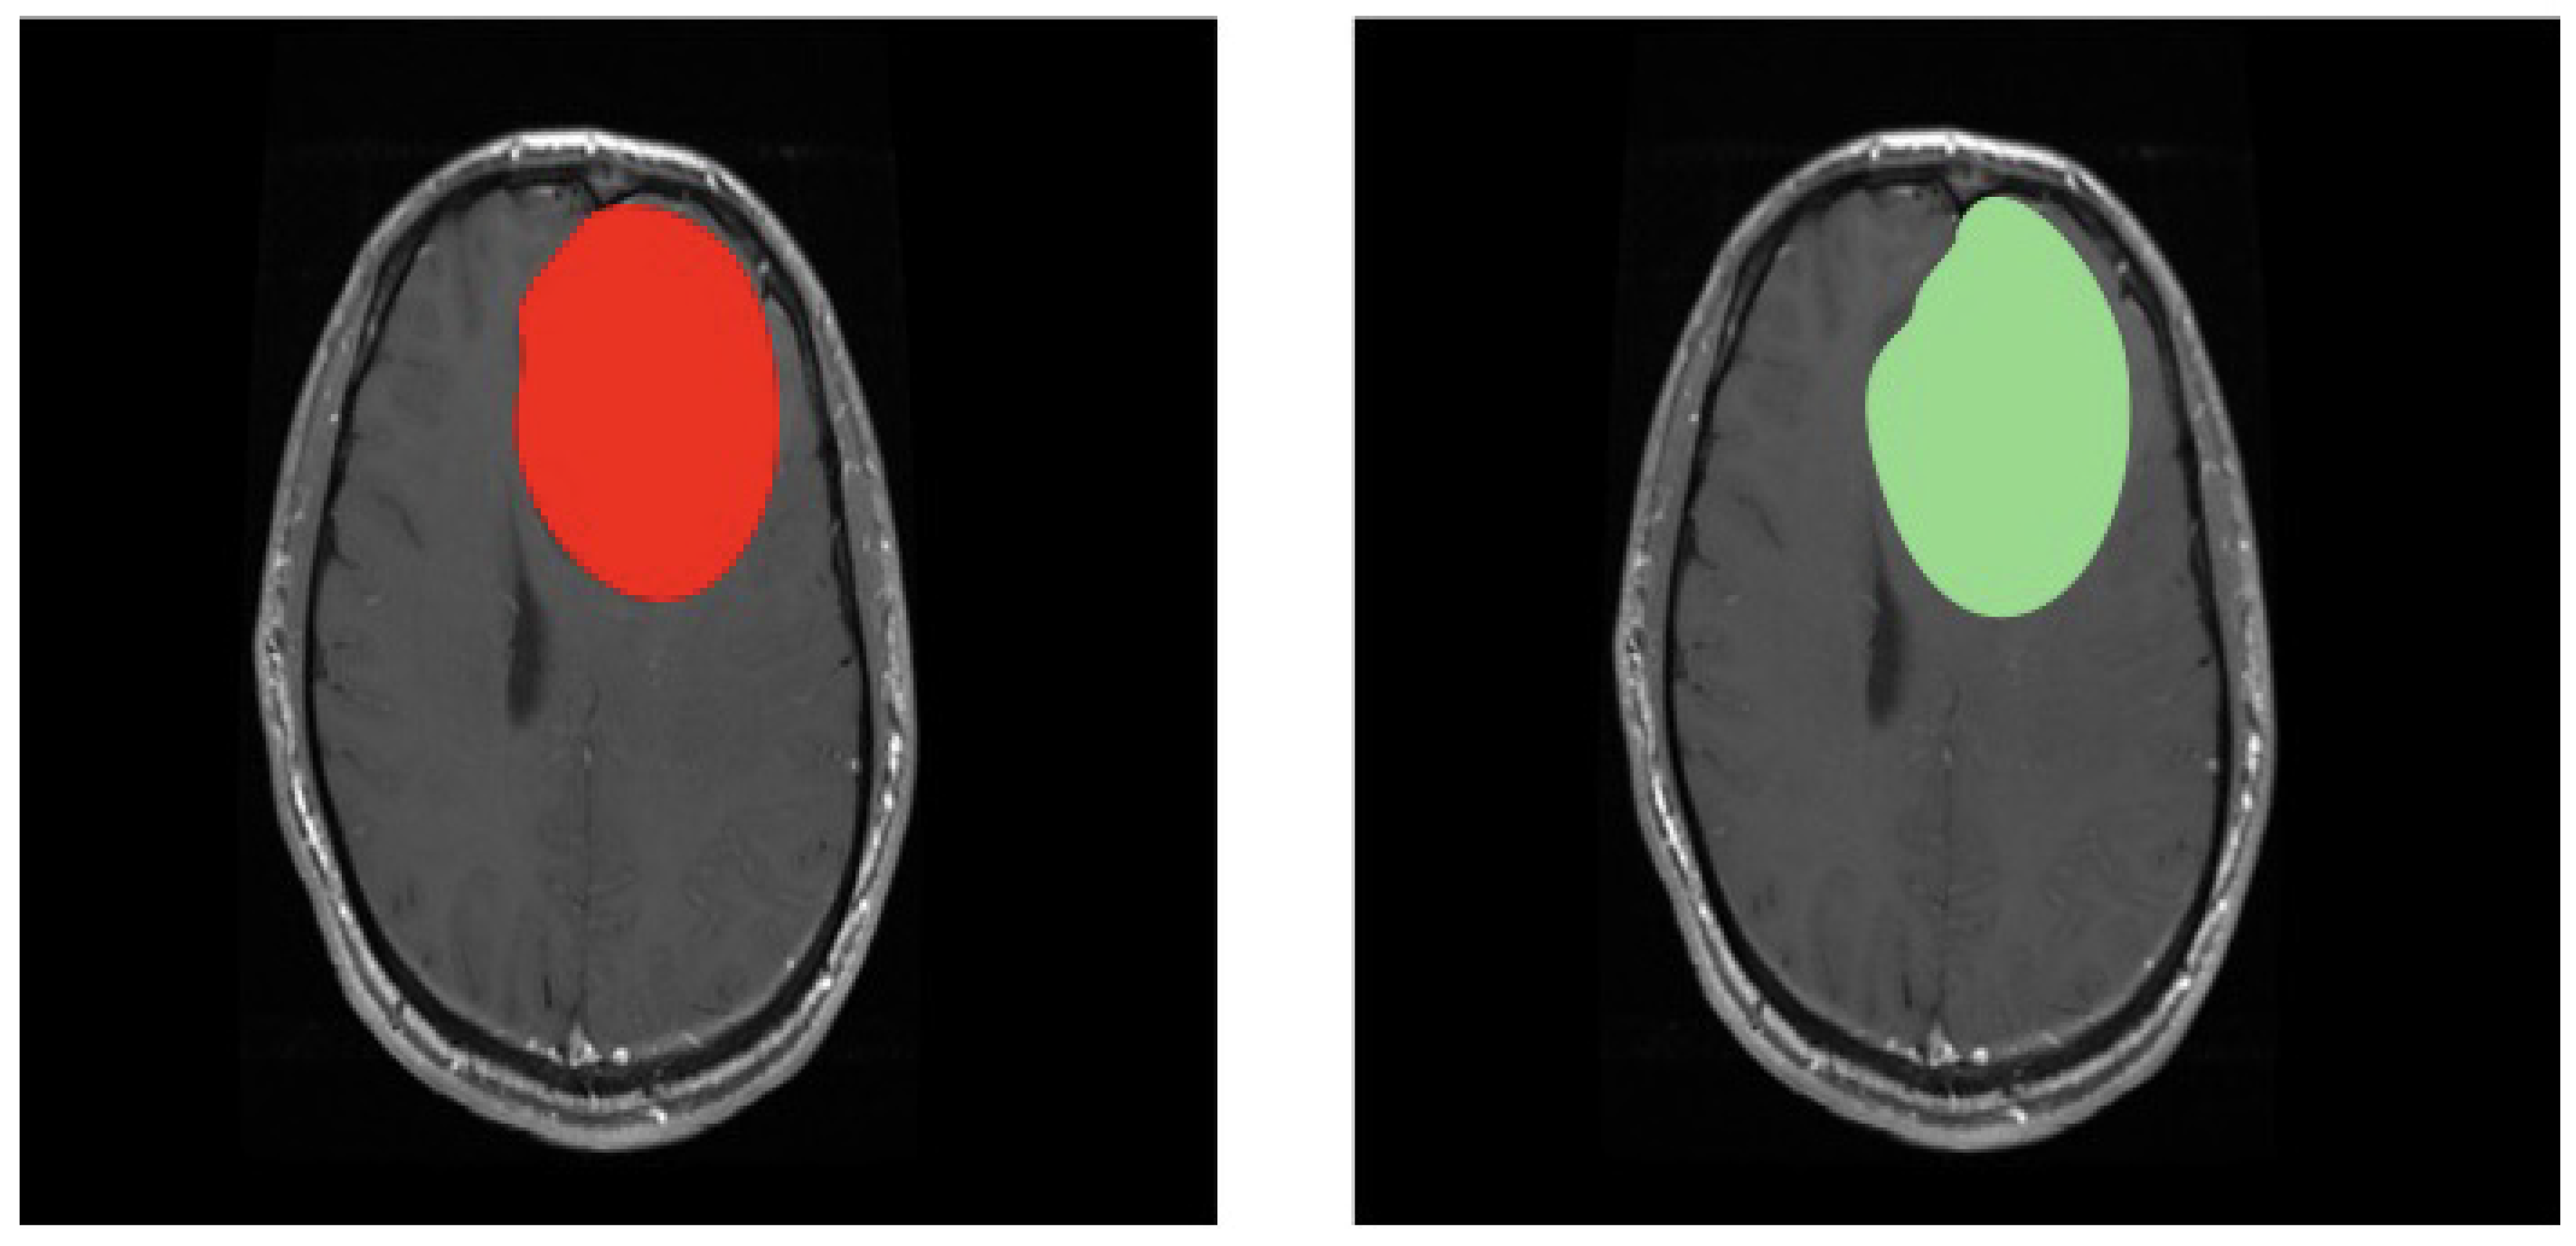

3.2. Second Scenario

3.3. Third Scenario